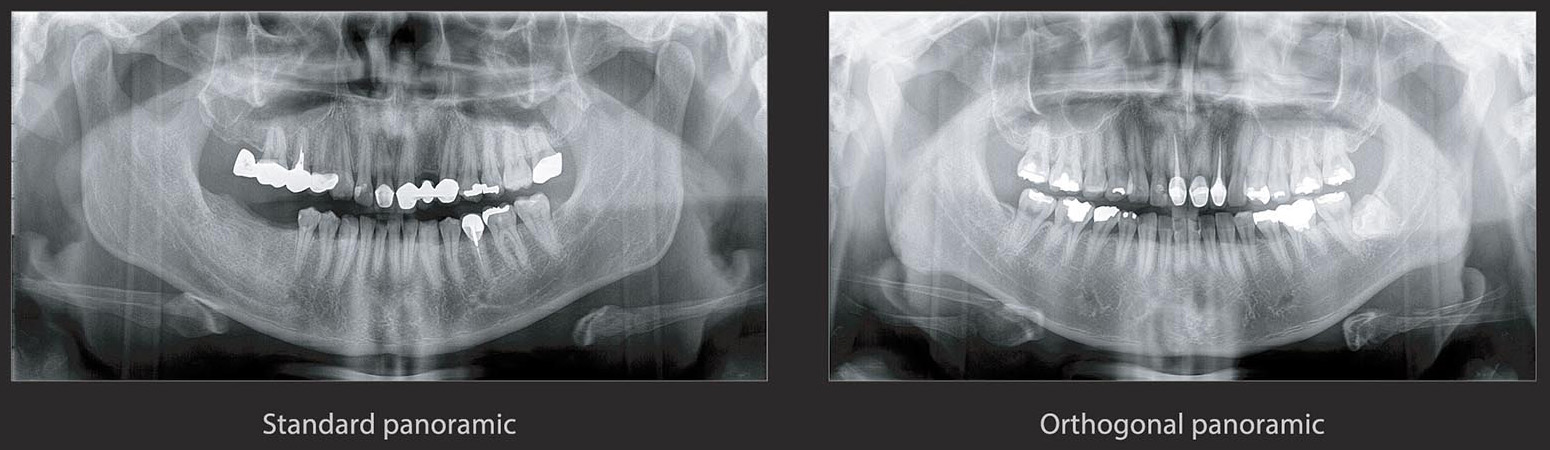

Panoramic

PAPAYA 3D PREMIUM PLUS 支援多樣的曝攝模式 , 以達到完整的診斷需求。

包含了:標準全口影像、 Orthogonal全口影像、咬翼全口(Bitewing)影像、兒童全口影像、TMJ雙剖面影像、TMJ前後雙影像、TMJ側面前後影像、TMJ側面前後雙影像、鼻竇側面影像、鼻竇前後影像。